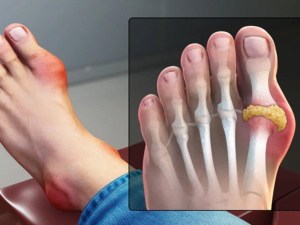

Подагра: як швидко полегшити біль і контролювати рівень сечової кислоти21.04.2026

Меновазан, Меновазан Саліцилат